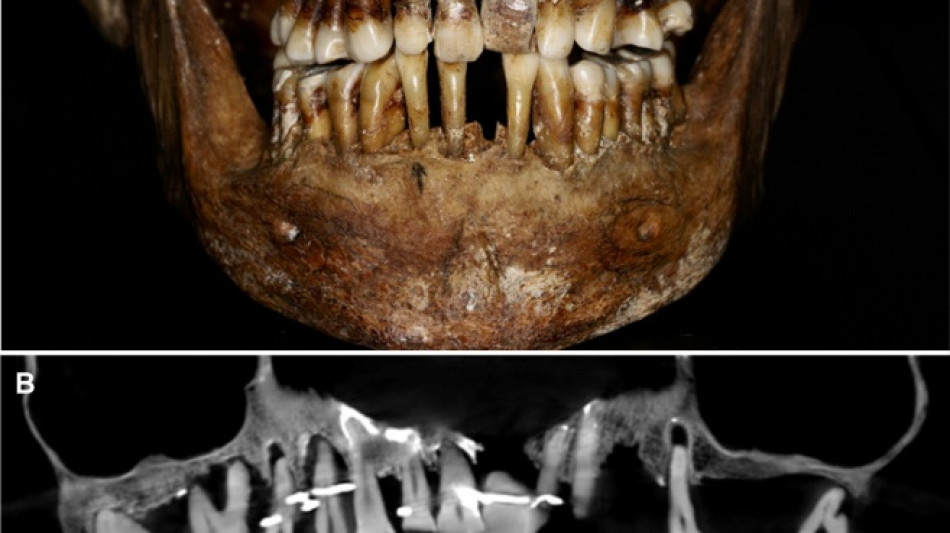

French aristocrat's golden dental secret revealed 400 years on

Scientists have discovered the long-buried secret of a 17th-century French aristocrat 400 years after her death: she was using gold wire to keep her teeth from falling out.

Embalmed in a lead coffin, her skeleton -- and teeth -- were remarkably well preserved.

At the time the archaeologists noticed that she had a dental prosthetic, but they did not have advanced scanning tools to find out more.

Thirty-five years later, a team of archaeologists and dentists have identified that d'Alegre suffered from periodontal disease that was loosening her teeth, according to a study published in the Journal of Archaeological Science: Reports this week.

A "Cone Beam" scan, which uses X-rays to build three-dimensional images, showed that gold wire had been used to hold together and tighten several of her teeth.

She also had an artificial tooth made of ivory from an elephant -- not hippopotamus, which was popular at the time.

But this ornate dental work only "made the situation worse", said Rozenn Colleter, an archaeologist at the French National Institute for Preventive Archaeological Research and lead author of the study.

The gold wires would have needed repeated tightening over the years, further destabilising the neighbouring teeth, the researchers said.